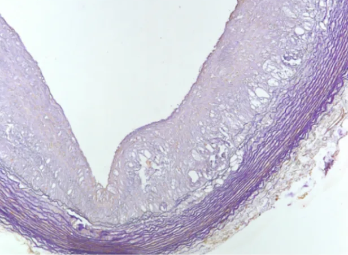

1.改良番红0-固绿法

用途及原理:利用嗜碱性的软骨与碱性染料番红O结合后呈现红色,而酸性的骨组织与酸性染料固绿结合后呈现绿色或蓝色。通过与呈现红色的软骨形成对比,可以清晰区分软骨组织和骨组织。